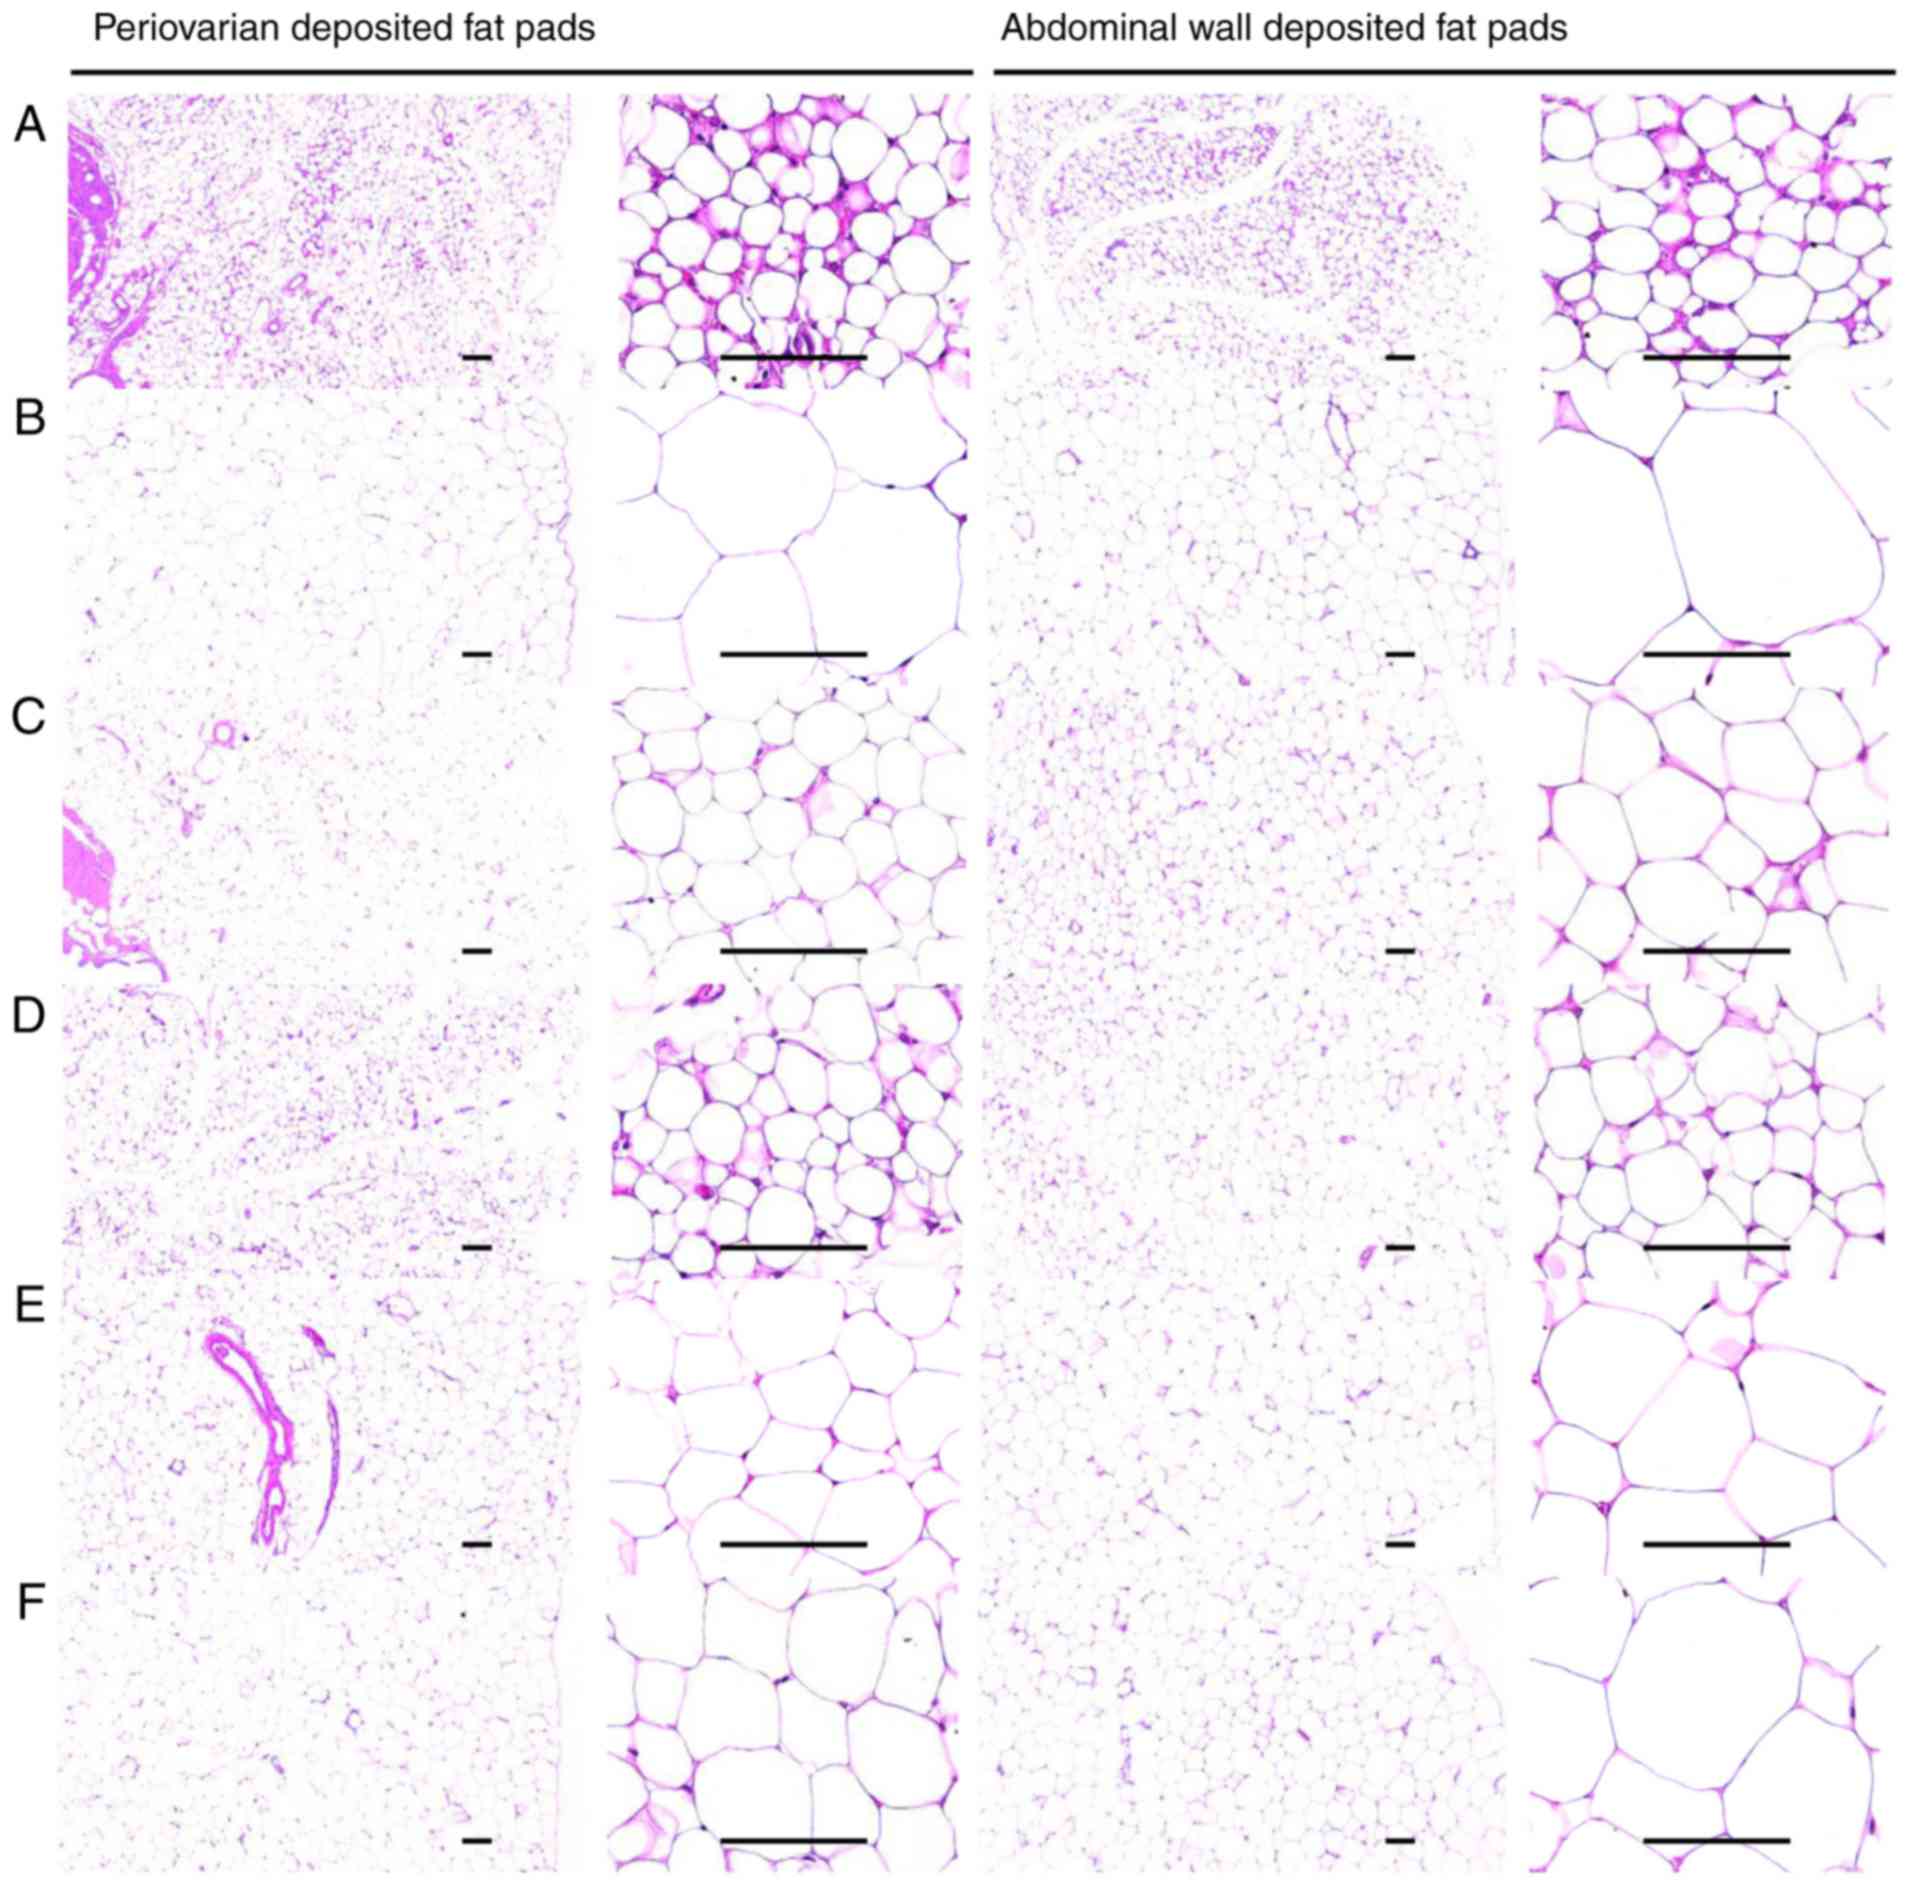

Effects on the adipocyte histopathology

(Table VII; Fig. 5).

A 104.72% increase in thickness of the stored

periovarian fat pad in the HFD control groups was observed compared

with in the healthy control, with changes of −38.57, −15.98, −23.09

and −37.65% in the metformin (250 mg/kg) and BHe (400, 200 and 100

mg/kg)-treated groups, respectively, compared with in the HFD

control mice. A 304.03% increase in the mean diameters of

periovarian white adipocyte tissues in the HFD control group was

observed, with changes of −61.79, −46.22, −53.51 and −64.27% in the

metformin (250 mg/kg) and BHe (400, 200 and 100 mg/kg)-treated

groups, respectively. An increase of 161.95% in the thickness of

the abdominal wall-stored fat pads was observed in the HFD control

groups, with changes of −43.09, −28.73, −32.28 and −40.97% in the

metformin (250 mg/kg) and BHe (400, 200 and 100 mg/kg)-treated

groups, respectively. The mean diameters of the abdominal

wall-stored fat pad white adipocyte tissues in the HFD control

group were increased by 255.71% compared with in the healthy

control mice, with changes of −50.05, −36.73, −43.27 and −53.98% in

the metformin (250 mg/kg) and BHe (400, 200 and 100 mg/kg)-treated

groups, respectively, compared with in the HFD control mice.